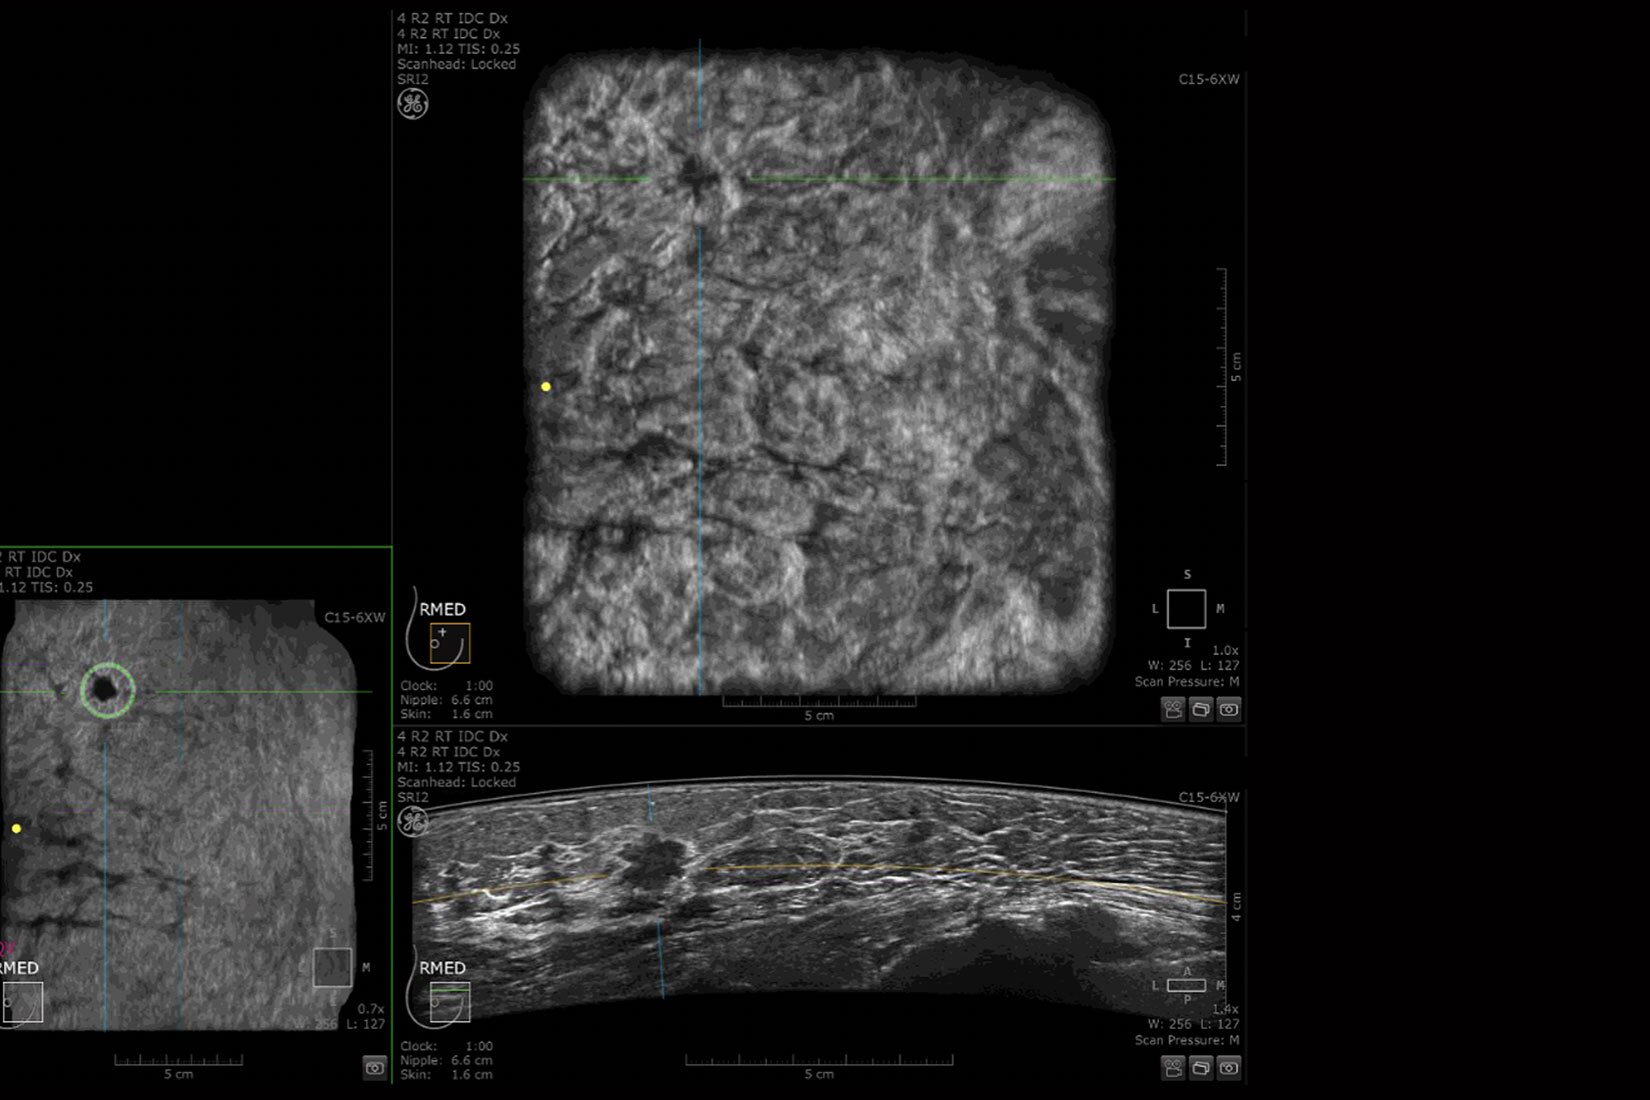

Accurate imaging for enhanced clinical confidence

Helping improve patient outcomes by reducing error rates, Venue’s imaging software is optimized to help the nerve stand out from other types of tissue. Allowing you to differentiate between the needle and patient anatomy with confidence, Venue family systems guide you with a real-time view of anatomy, needle advancement and local anesthetic spread.

Improved visualization with Needle Recognition

Needle Recognition also allows you to easily differentiate between the needle and patient anatomy with confidence—allowing you to quickly guide the needle exactly where it needs to be and helping to minimize patient discomfort.